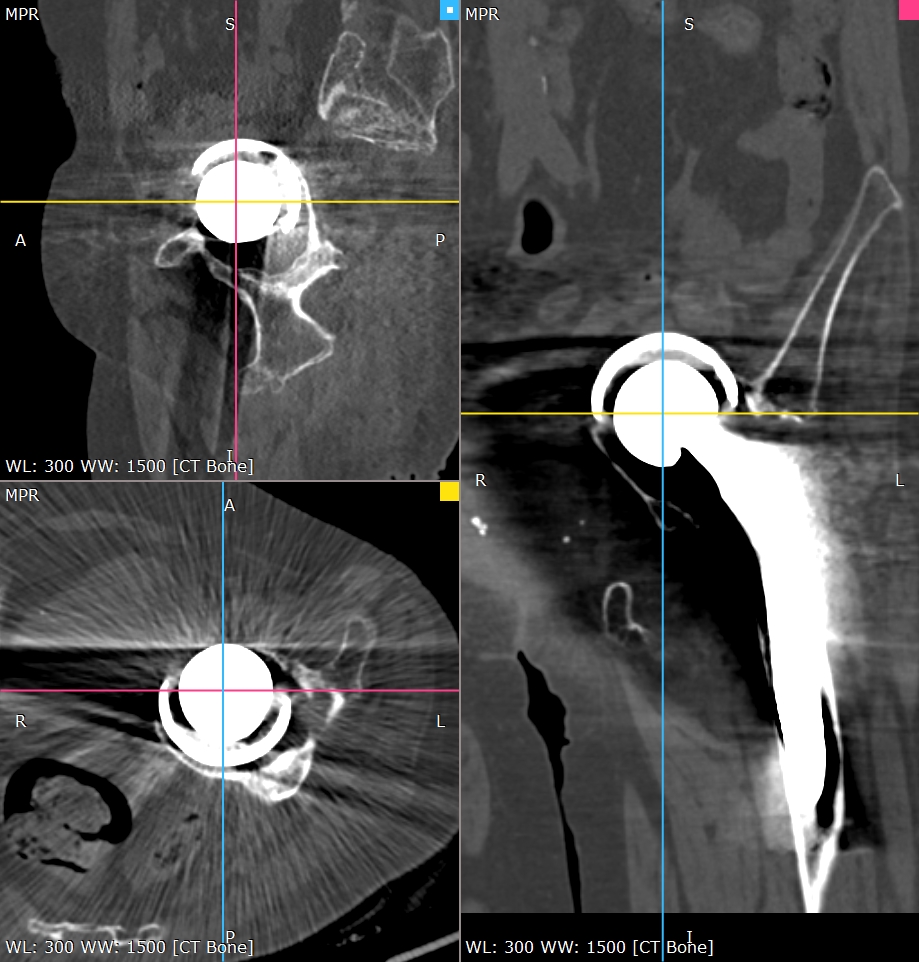

患者老年女性,类风湿性关节炎,骨质疏松,双侧全髋术后,髋臼假体移位至盆腔多年,不能行走。(The patient is an elderly female with rheumatoid arthritis and osteoporosis. After bilateral total hip surgery, the acetabular prosthesis has been displaced into the pelvic cavity for many years and she is unable to walk.)